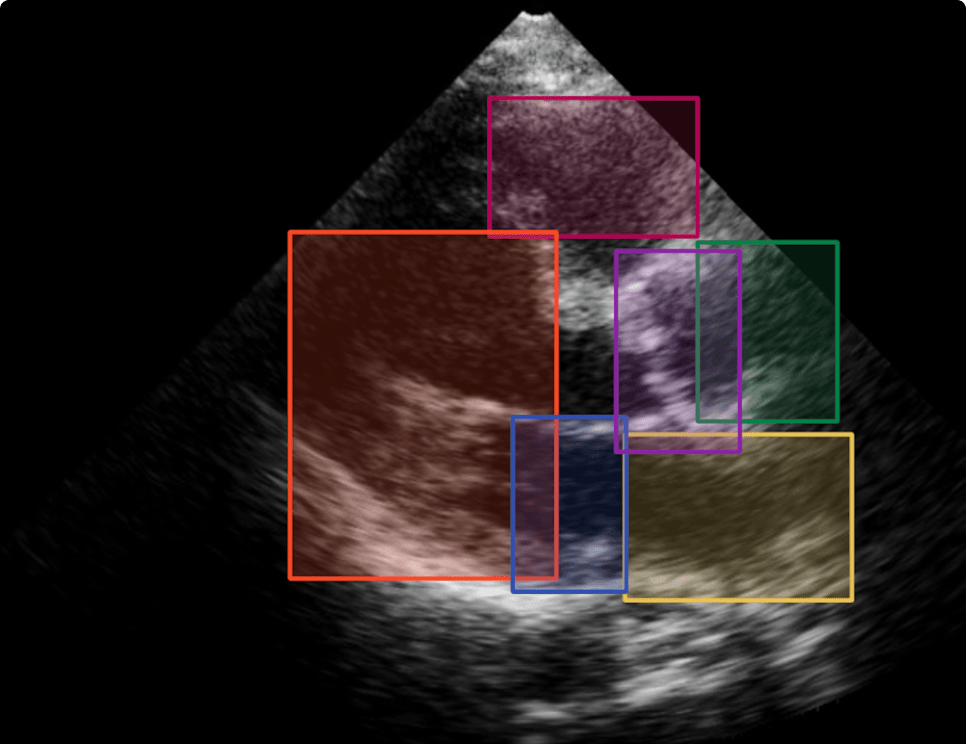

超声波成像

超声成像是利用超声波呈现不透明物内部形象的技术。医疗企业利用大量的超声波图片对病灶进行标注,并进行模型训练,以此来辅助医生进行病人的病情判断。